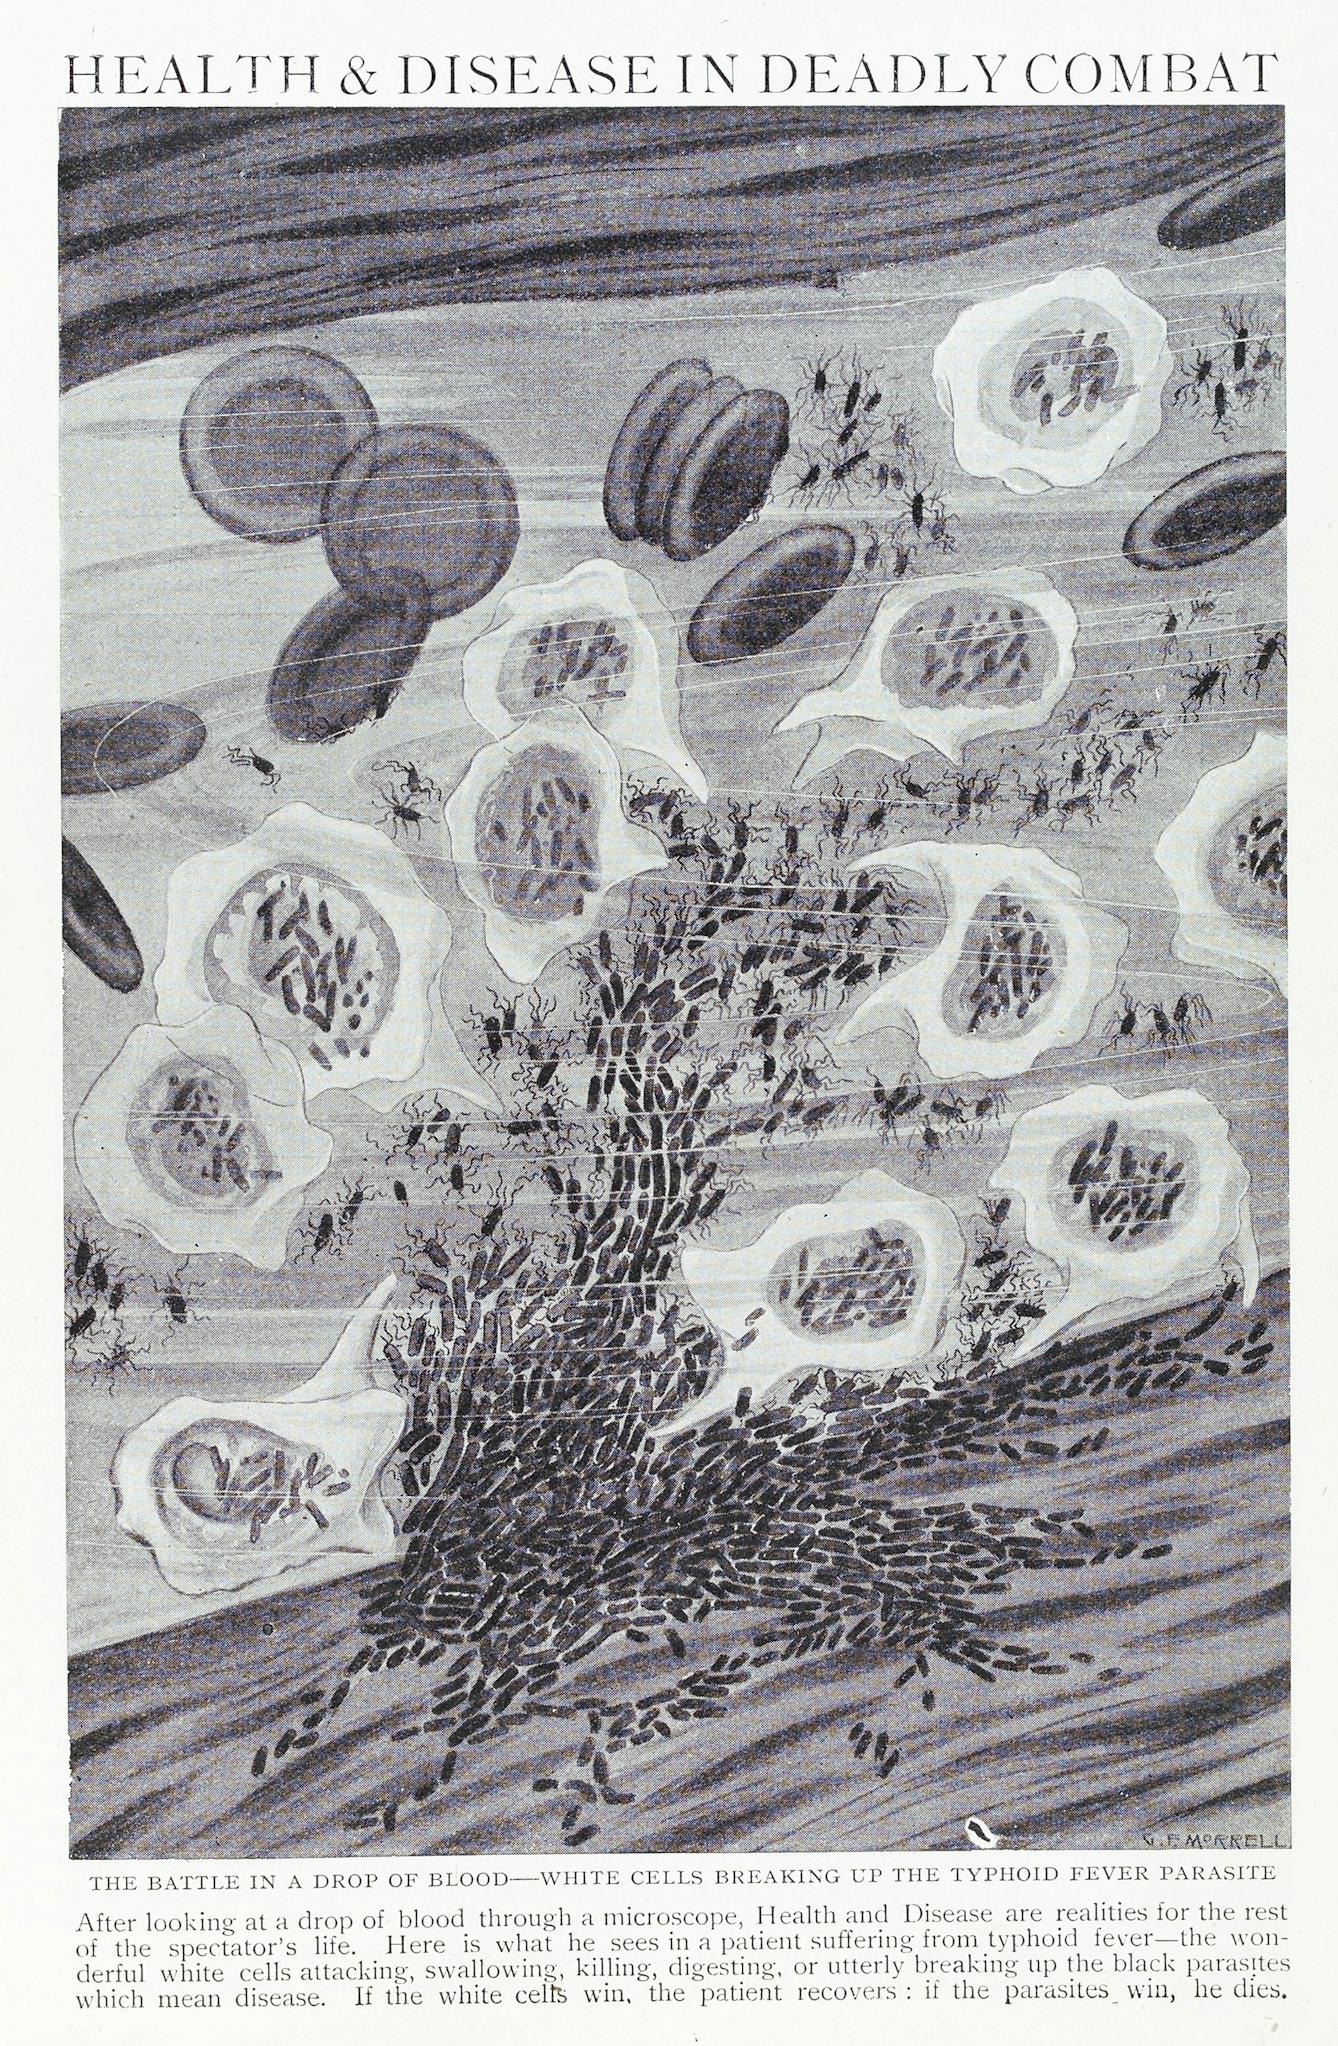

White blood cells attacking typhoid in the bloodstream, 1912.